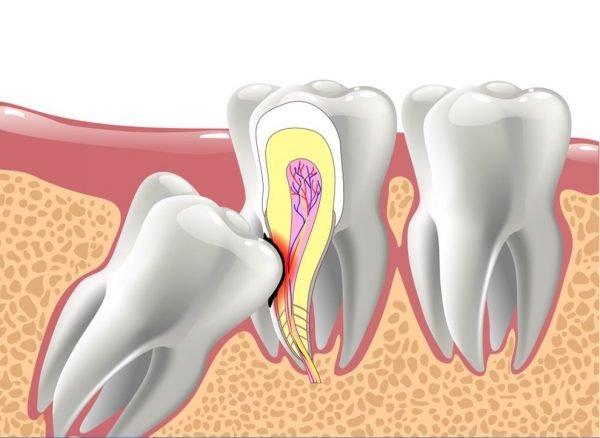

Cấu tạo của răng khôn

Răng khôn gồm có thân răng và chân răng. Thân răng là phần răng nằm phía trên nướu, còn chân răng là phần nằm dưới xương hàm, nó được giữ chặt bởi các dây chằng nha chu. Răng khôn có số lượng chân không cố định. Số lượng chân còn tùy thuộc loại răng và vị trí của răng. Cũng giống như những chiếc răng khác, răng khôn có cấu tạo gồm 3 phần:

- Men răng: Men răng là lớp ngoài cùng bao bọc thân răng. Men răng được cấu tạo từ 96% chất vô cơ, cứng cáp và có thể chịu được những tác động mạnh.

- Ngà răng: Ngà răng là phần nằm trong men răng, có màu vàng nhạt, hơi xốp và có tính thấm, có độ cứng không bằng men răng. Đây là bộ phận chiếm phần lớn khối lượng răng. Ngà răng được cấu tạo từ 70% chất vô cơ, 30% là chất vô cơ và nước. Ngoài ra, trong ngà răng còn chứa các ống thần kinh nên khá nhạy cảm với các tác động nhiệt độ nóng, lạnh bên ngoài.

- Tủy răng: Phần nằm trong buồng tủy và ống tuỷ, có chứa các mạch máu, dây thần kinh, mạch hạch,… giúp vận chuyển các chất dinh dưỡng nuôi răng.

3. Số chân răng khôn khác nhau

Có một sự thật nữa mà có lẽ bạn chưa biết. Đó là về số lượng chân của răng khôn.

Không phải răng khôn nào cũng có cấu tạo giống nhau. Trong khi răng khôn hàm dưới chỉ có 2 chân, thì răng khôn hàm trên có đến 3 chân. Vì vậy mà khi nhổ răng khôn, bạn có thể kiểm tra lại số lượng mảnh răng cắt được lấy ra. Điều này sẽ đảm bảo tránh được rủi ro lấy thiếu chân răng ở một số địa chỉ nha khoa thiếu chuyên nghiệp.